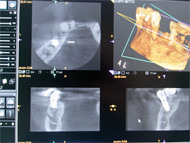

【歯科用3DCT】

3D画像では、高度歯科治療(インプラントや歯周病など)の診断に有効であり、従来のレントゲンの平面画像では難しいとされたものの確認などが行えます。

エックス線の照射時間と撮影領域を必要最小限まで抑えたレントゲンで3D撮影を行っております。